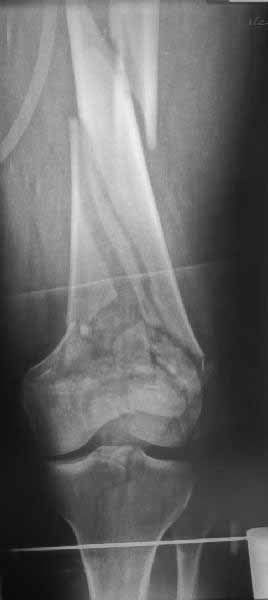

Ответ на эту часть Вашего поста – вложенный файл. Больная оперирована неделю назад по поводу открытого перелома дистального эпиметафиза бедренной кости. После операции она идёт в рентгенкабинет для выполнения послеоперационной контрольной рентгенографии, представленной на слайдах 10 и 11. Узнав, почему её фотографируют, просила передать Вам, Антон, привет.